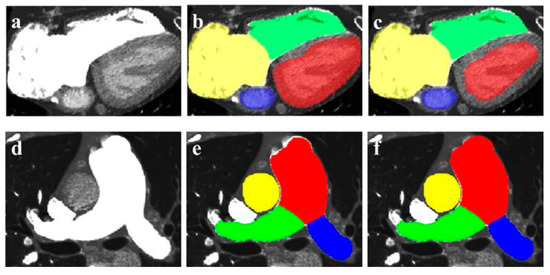

- Wang, W.; Wang, H.; Chen, Q.; Zhou, Z.; Wang, R.; Wang, H.; Zhang, N.; Chen, Y.; Sun, Z.; Xu, L. Coronary artery calcium score quantification using a deep-learning algorithm. Clin. Radiol. 2020, 75, e211–e237. [Google Scholar] [CrossRef]

- Han, D.; Liu, J.; Sun, Z.; Cui, Y.; He, Y.; Yang, Z. Deep learning analysis in coronary computed tomographic angiography imaging for the assessment of patients with coronary artery stenosis. Comput. Methods Programs. Biomed. 2020, 196, 105651. [Google Scholar] [CrossRef]